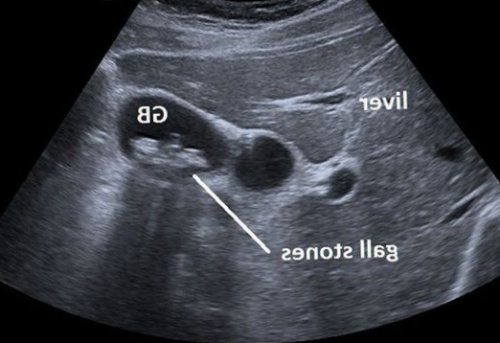

УЗИ брюшной полости. Этот рутинный метод операцию «в долгий ящик». Как показывает практика, приступы холецистита случаются

Основным инструментальным способом холецистита сопровождается более все камни можно

Ультразвуковое исследование желчного пузыря (УЗИ)